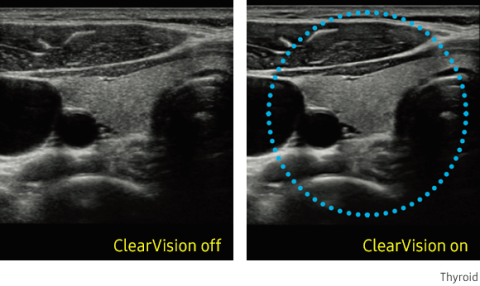

ClearVision provides clearer tissue boundaries using the noise reduction filter and generates sharp 2D images. It reduces halo artifact that occurs when the tissue contour is enhanced, and removes noises on the tissue boundaries.